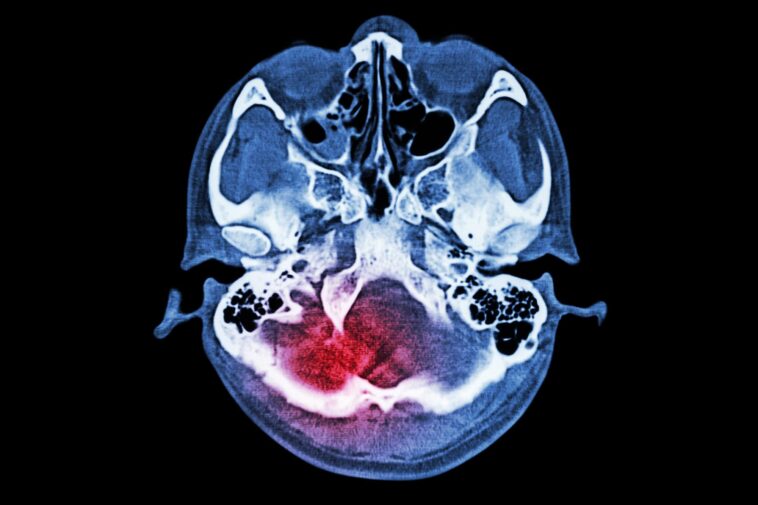

Cartes cérébrales IRM fonctionnelles de la connectivité fonctionnelle à l'état de repos chez des participants représentatifs de même âge et sexe. (A, B) Les vues axiales (en haut) et coronales (en bas) montrent la connectivité du cerveau entier, avec la graine dans la région frontale supérieure gauche (L), chez une participante de 36 ans à la luminothérapie de faible niveau. (LLLT) (A) et une participante de 38 ans au groupe de traitement fictif (B) pendant les phases aiguë, subaiguë et subaiguë tardive (colonnes, de gauche à droite, dans A et B) de guérison d’un traumatisme crânien. (C) Les vues axiales (en haut à gauche), coronales (en bas à gauche) et sagittales (à droite) chez une participante témoin de 38 ans sont présentées à des fins de comparaison ; le cercle vert plein dans la vue sagittale indique l’emplacement de la région graine frontale supérieure gauche. La barre de couleur indique que les régions cérébrales aux couleurs chaudes (rouge, orange, jaune) présentent des fluctuations à l'état de repos qui ont une corrélation positive significative (r de 0 à 1) avec celles de la région frontale supérieure gauche et les régions cérébrales aux couleurs froides ( bleu) montrent des fluctuations à l’état de repos qui ont une corrélation négative significative (r de −1 à 0) avec celles de la région frontale supérieure gauche. Les régions cérébrales qui ont une connectivité fonctionnelle avec la graine frontale supérieure gauche chez le participant traité par LLLT (pointes de flèches en A) mais pas chez le participant traité de manière factice (pointes de flèches en B) sont présentées. La flèche en A montre en outre des régions cérébrales présentant une corrélation positive avec la graine chez le participant traité par LLLT, mais une corrélation négative avec la graine chez le participant traité de manière factice (flèche en B). Crédit : Société radiologique d'Amérique du Nord (RSNA)